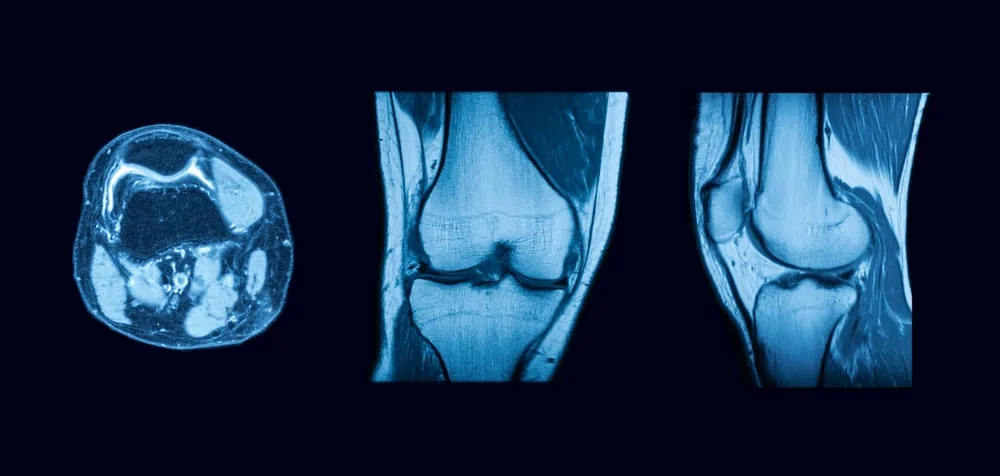

A great example of this is a study where dozens of biomarkers in knee tissues were measured to predict responses to a particular procedure. Human analysis couldn’t make sense of the data, but when a machine learning algorithm was applied, it uncovered specific chemical profiles that correlated with better patient outcomes. This ability to detect patterns in chaotic data is precisely why AI is the next frontier in medical imaging.

Imagine a scenario where an AI system reads the raw data from an MRI scan and directly correlates it with specific diagnoses or treatment outcomes. For example, an AI system could predict who is likely to need knee replacement surgery in the next five years or identify patients who will respond positively to treatments like platelet-rich plasma (PRP) injections. This level of predictive capability could drastically improve treatment plans and patient outcomes.

In fact, there are already AI systems that can analyze MRI scans of the knee and predict the likelihood of lesions or even detect early markers for heart disease—all from the same images used to diagnose musculoskeletal conditions. These advancements signal the future of MRI: a future where AI doesn’t just assist radiologists but takes over the complex task of analyzing raw data, making diagnoses, and recommending treatments based on patterns that humans would struggle to identify.